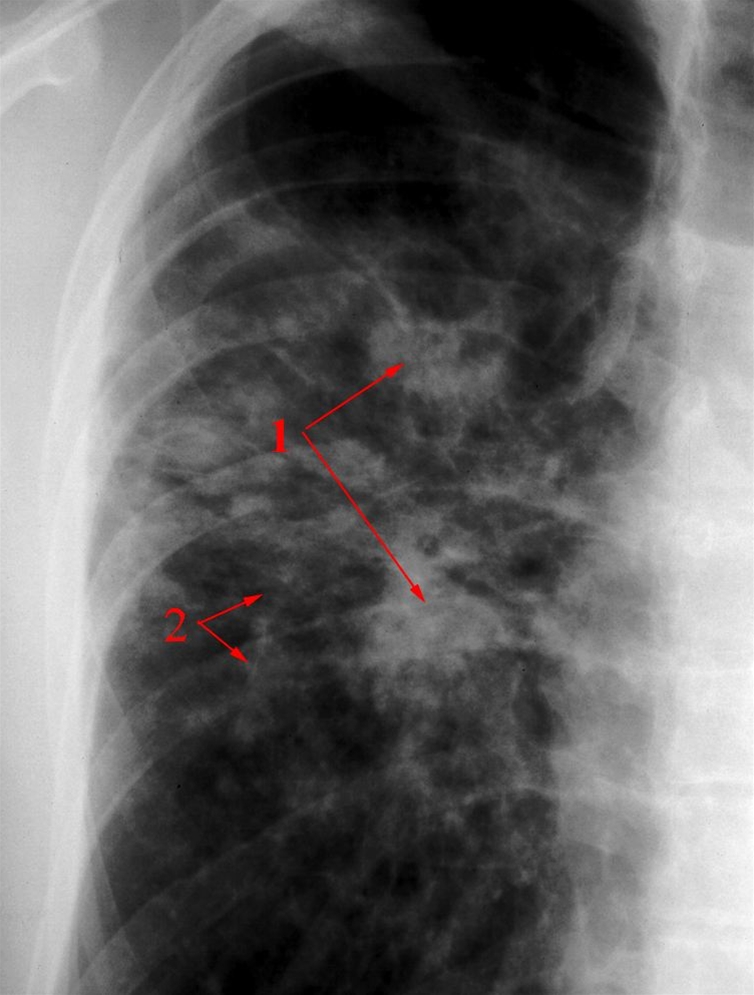

Lunger, røntgen, sarkoidose

Multiple knuder i varierende størrelser (1), samt stribeformede fibrøse strøg (2). Typisk fordeling perihilært (centralt).